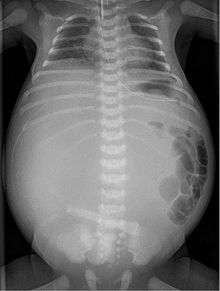

X-ray of a newborn with meconium pseudocyst resulting from bowel perforation. In this case the cause was atresia of the terminal ileum. There is a fine rim of calcification surrounding the big pseudocyst which shifts the other intestinal structures outwards.

Meconium peritonitis refers to rupture of the bowel prior to birth, resulting in fetal stool (meconium) escaping into the surrounding space (peritoneum) leading to inflammation (peritonitis). Despite the bowel rupture, many infants born after meconium peritonitis in utero have normal bowels and have no further issues.

Twenty percent of infants born with meconium peritonitis will have vomiting and dilated bowels on x-rays which necessitates surgery.

Meconium peritonitis is sometimes diagnosed on prenatal ultrasound[1] where it appears as calcifications[2] within the peritoneum.